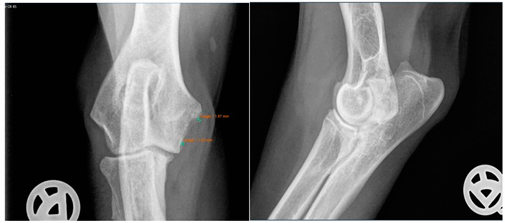

Moreover, Trochlear Notch Sclerosis (TNS), a radiological term denoting increased bone radio-opacity in the ulnar trochlear notch region, was quantified. The measurements adhered to the methodology outlined by Draffan et al. [

13], and the comprehensive TNS ratio of sclerosis to the ulnar depth was subsequently computed (

Figure 1). All measurements were performed by the first author of the article.

Viewing the TNS, both intra- and inter-individual calculations were carried out. Hence, for the intra-individual observations, the difference was calculated for each dog and the median was calculated from these results. Paired (intra-individual), the TNS had increased by 0.04 mm for the median of the arthroscopic-treated elbows. Without considering the intra-individual differences, the median TNS value for the arthroscopic-treated elbows was 0.47 mm pre-operatively and 0.53 mm post-operatively. The p-value showed statistical significance (p = 0.022) for the TNS value comparing the pre- vs. post-therapy conditions for this group. For the conservatively treated elbows, the median TNS did not change when the intra-individual differences were formed (comparing before and after therapy; median = 0), but without considering the intra-individual differences, the median TNS value pre-operatively was 0.45 mm and post-operatively 0.50 mm. There was no significant difference in the TNS value of the elbows treated conservatively (p = 0.228). If the TNS value increased intra-individually, the enlargement was quite more evident compared to the elbows, with a reduction in the TNS value (maximum reduction in the TNS value is stratified after conservative or arthroscopic treatment at 0.07 mm or 0.08 mm, respectively, whereas the maximum enlargement is 0.12 mm or 0.20 mm, respectively).